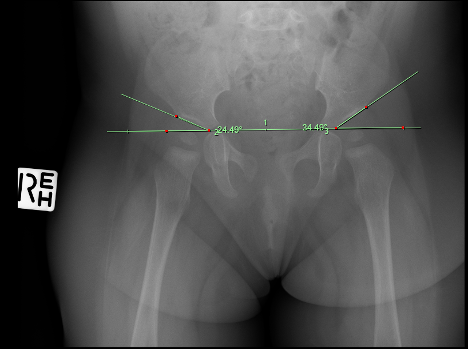

Pediatrics | Jul 16, 2025

Guideline discordance in the management of a toddler with Developmental Dysplasia of the Hip

Background: Guidelines are used in clinical practice to provide clear direction and supporting evidence for a range of conditions pertinent...Read More